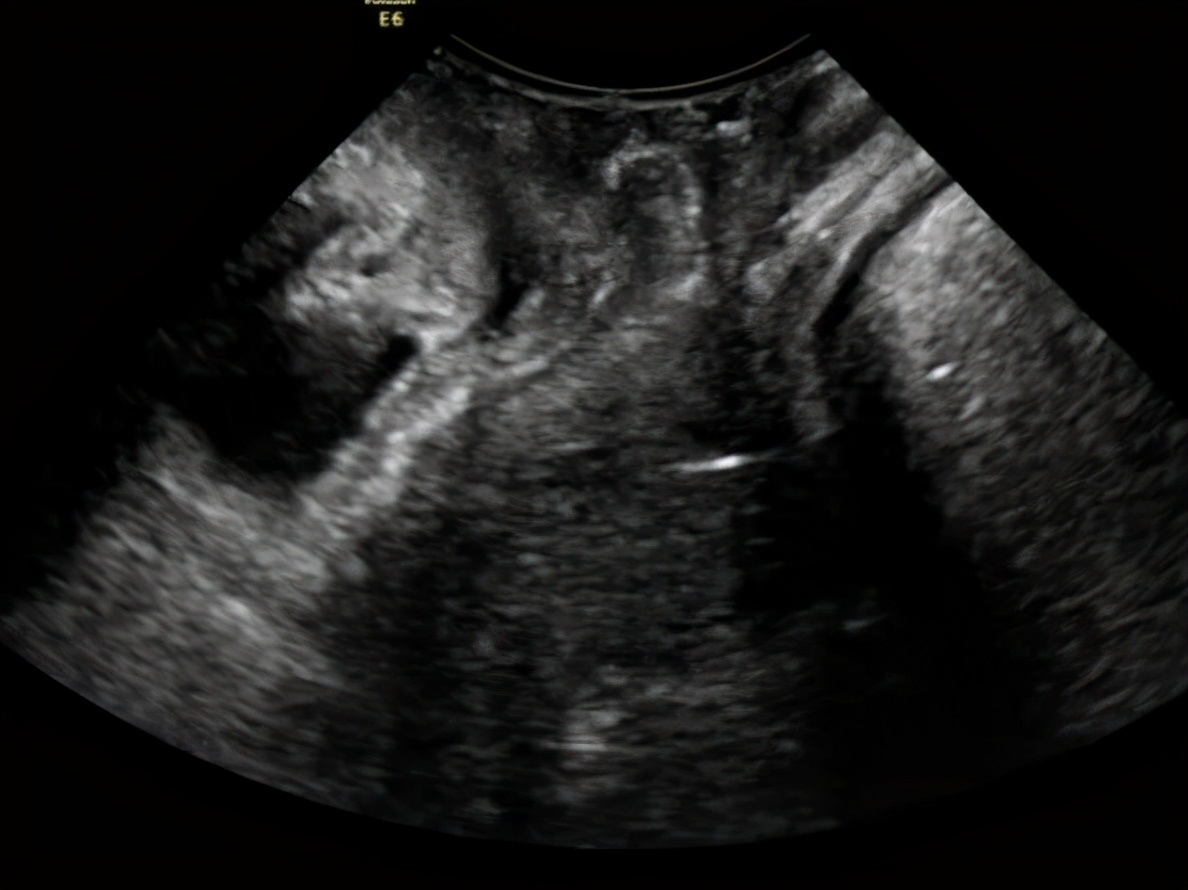

王阿姨的检查结果

(静息状态)